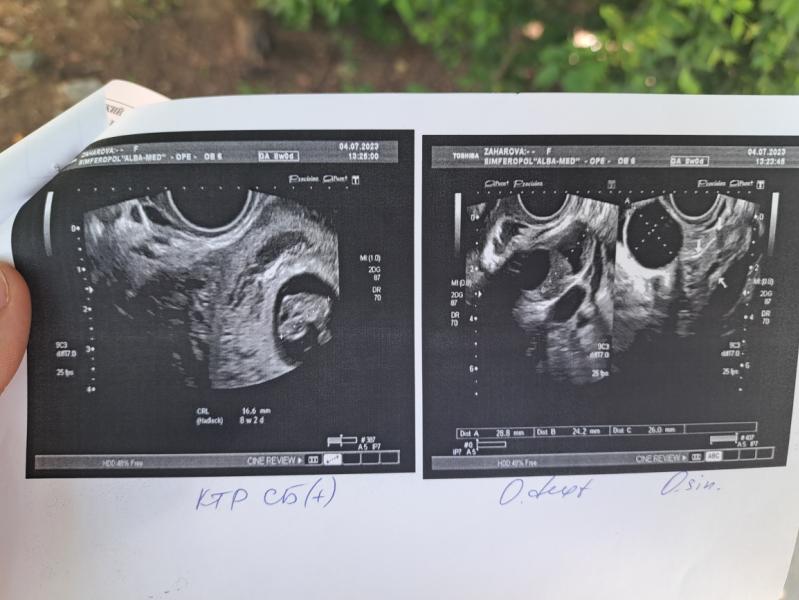

Всем приветик, мы растем и развиваемся день за днем, сегодня ездила на УЗИ, Из-за проьлем с яичниками(кисты есть), приходится мучиться , таблетки, свечи и проверочные УЗИ...

Лёгкой беременности🥰 у вас 8 недель и чсс 181 а у меня 12 недель и чсс 169, что-то меня настораживает или это все беременные загоны🤪